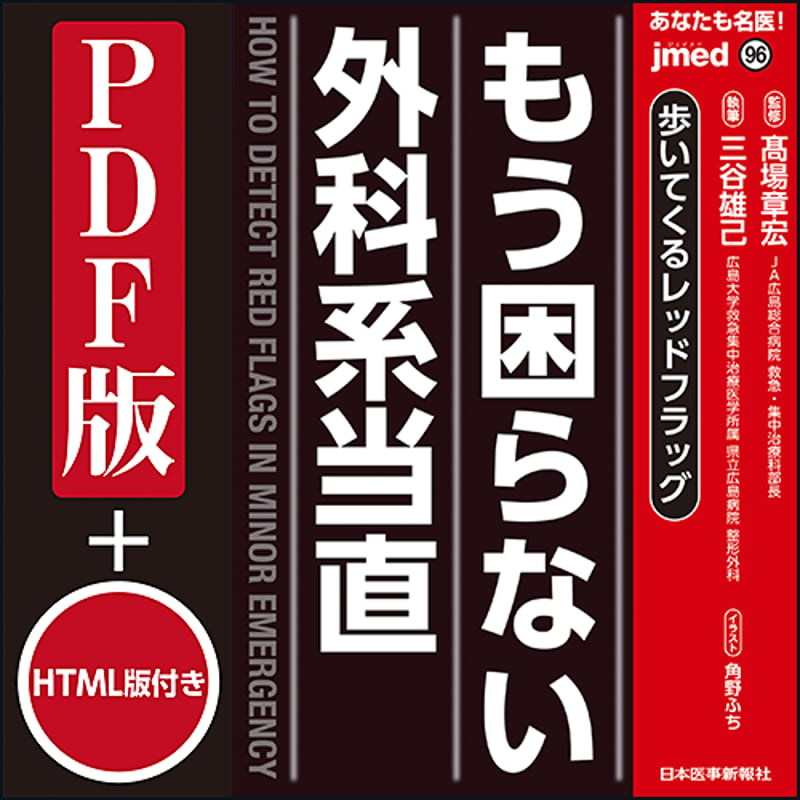

Amazon.co.jp: 内科 2021年9月増大号(Vol.128 No.3)意外と知られていない !? 自科の常識・他科の非常識 : Japanese Books, jmedmook96 歩いてくるレッドフラッグ もう困らない外科系当直 | 日本医事新報社 W,

jmedmook96 歩いてくるレッドフラッグ もう困らない外科系当直 | 日本医事新報社 W, 2ページ目) 「命をつなぐ行為」 “透析大国”日本、一方で進まない患者への理解 「“輸血に使われたくないから献血しない”という誤った知識も…」 | 国内 | ABEMA TIMES | アベマタイムズ,